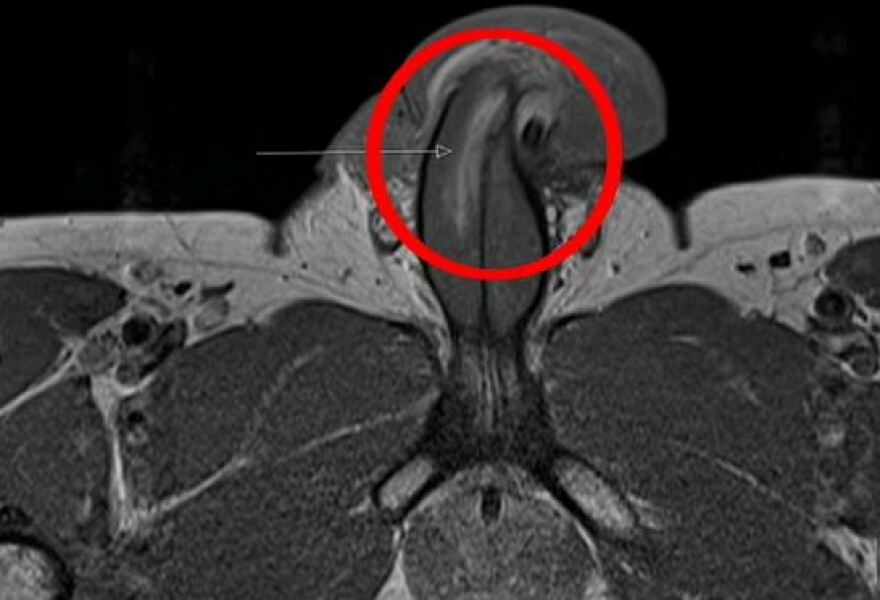

Όσο κι αν ακούγεται απίστευτο, ένας Βρετανός υπέστη «κάταγμα πέους» κατά την διάρκεια της σεξουαλικής πράξης με την μαγνητική τομογραφία να δείχνει κάθετη ρωγμή στο μόριο του.

Κατά την διάρκεια της εξέτασης, οι γιατροί εντόπισαν μία ρωγμή τριών εκατοστών κατά μήκος της δεξιάς πλευράς του ανδρικού μορίου με την βοήθεια της μαγνητικής τομογραφίας, όπως αναφέρει η βρετανική εφημερίδα Daily Mail.